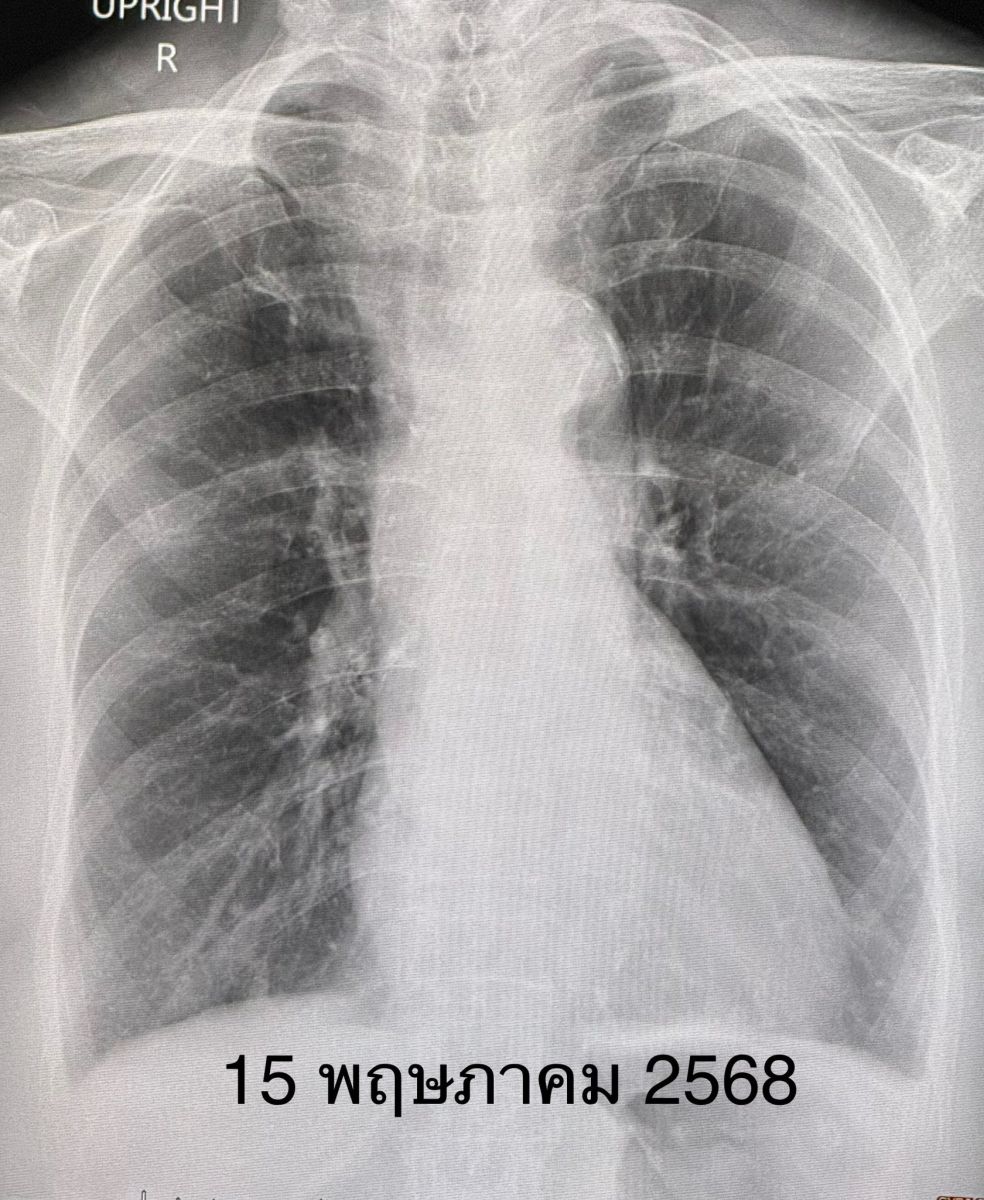

วินิจฉัย : ปอดอักเสบเล็กน้อยจากโรคโควิด-19 ให้ยาต้านไวรัส เรมเดซิเวียร์ (Remdesivir) ฉีดเข้าทางหลอดเลือดดำ ไข้สูงลอย 3 วันแรก หลังได้ยาเรมเดซิเวียร์ 3 วัน ไข้เริ่มลงและเอกซเรย์ปอดเริ่มดีขึ้น ให้ยาฉีดต่อจนครบ 5 วัน ไม่มีไข้ ไอดีขึ้นมาก เอกซเรย์ปอดอักเสบหายเป็นปกติ (ดูรูป) กลับบ้านได้ในเวลา 5 วัน

ในปัจจุบันคนติดเชื้อโควิด-19 ส่วนใหญ่มีอาการน้อยเหมือนหวัดธรรมดา ไม่ต้องกินยาต้านไวรัสก็หายเองได้ แต่ก็มีบางคนที่เชื้อไวรัสโควิด-19 ลงปอดได้ แต่ไม่หนักเหมือนกับการระบาดรอบแรกๆ อย่างในผู้ป่วยรายนี้มีไข้สูง มีปอดอักเสบเล็กน้อย ไม่เหนื่อย ไม่ต้องให้ออกซิเจน ตอบสนองดีมากต่อยาต้านไวรัสเรมเดซิเวียร์ ปอดอักเสบหายเป็นปกติภายในเวลา 5 วัน